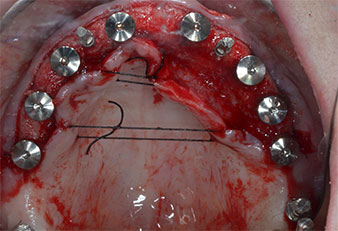

Debido al hueso relativamente duro (D2) existente en el sector anterior, los sitios de los implantes largos de 10 mm de las posiciones 11 y 21 se finalizaron con una fresa rotatoria de 4 mm de diámetro, en combinación con un contra-ángulo quirúrgico WS-75 L de W&H, el motor de implantes Implantmed de W&H y el módulo opcional Osstell ISQ de W&H. En cambio, debido a la existencia de hueso blando, los sitios posteriores se prepararon hasta un diámetro final de 3 mm utilizando el inserto Piezomed I3P. Por último, los implantes se colocaron a nivel crestal para su osteointegración durante tres meses (figuras 6-10). La prótesis existente se mantuvo sobre cuatro implantes provisionales (figura 8).

Se ha demostrado que la preparación piezoeléctrica mejora la cicatrización ósea (6, 7), lo que se traduce en una mejor formación de hueso y una mayor densidad ósea cerca de la superficie del implante (8). Tal como se demostró en un ensayo controlado aleatorizado, esto puede provocar un aumento más temprano de la estabilidad secundaria del implante que en los sitios preparados con instrumentos rotatorios (4).

Otro aspecto importante de la preparación piezoeléctrica es la excelente sensibilidad del cirujano en volúmenes óseos pequeños, como sucedió en el caso de la paciente que hemos descrito aquí. También nos permite corregir la angulación del lecho óseo con todos y cada uno de los instrumentos antes de la colocación del implante.